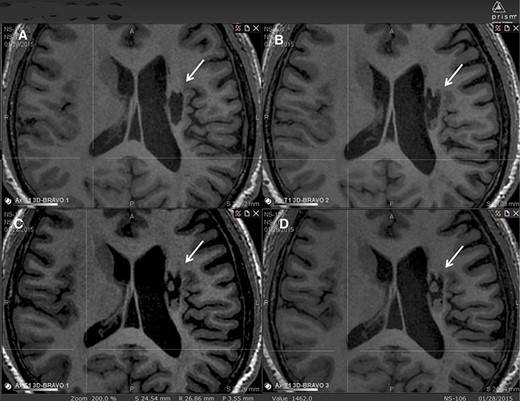

在6個(gè)月的隨訪中,所有9名受試者均觀察到新組織,源自腦軟化梗塞腔。該腔內(nèi)組織外觀具有以下特征:短期活力(術(shù)后第一次MRI與基線相比的組織外觀)—9例中有9例;生長(zhǎng)(術(shù)后至少兩次MRI中新組織增加)—6例中有6例;穩(wěn)定(術(shù)后至少兩次MRI中新組織無(wú)變化;即生長(zhǎng)平臺(tái)期,最長(zhǎng)為24個(gè)月)—6例中有5例;無(wú)法獲得24個(gè)月后的長(zhǎng)期活力。圖2顯示了腔內(nèi)組織生長(zhǎng)的縱向MRI示例。9名受試者的梗塞腔內(nèi)這種無(wú)關(guān)組織的存在都很明顯(圖3)

圖2:腔內(nèi)組織生長(zhǎng)的縱向MRI示例。

圖中顯示了B組 (#106) 受試者在T1MRI上隨時(shí)間的變化。

(A):基線時(shí),(B) 6個(gè)月隨訪時(shí),(C) 12個(gè)月隨訪時(shí),(D) 24個(gè)月隨訪時(shí)。箭頭表示梗塞腔。

可以看到兩個(gè)組織團(tuán)塊,在基線時(shí)不存在,推測(cè)是來(lái)自植入的NSI-566,隨著時(shí)間的推移,它們似乎慢慢填滿了腔體。